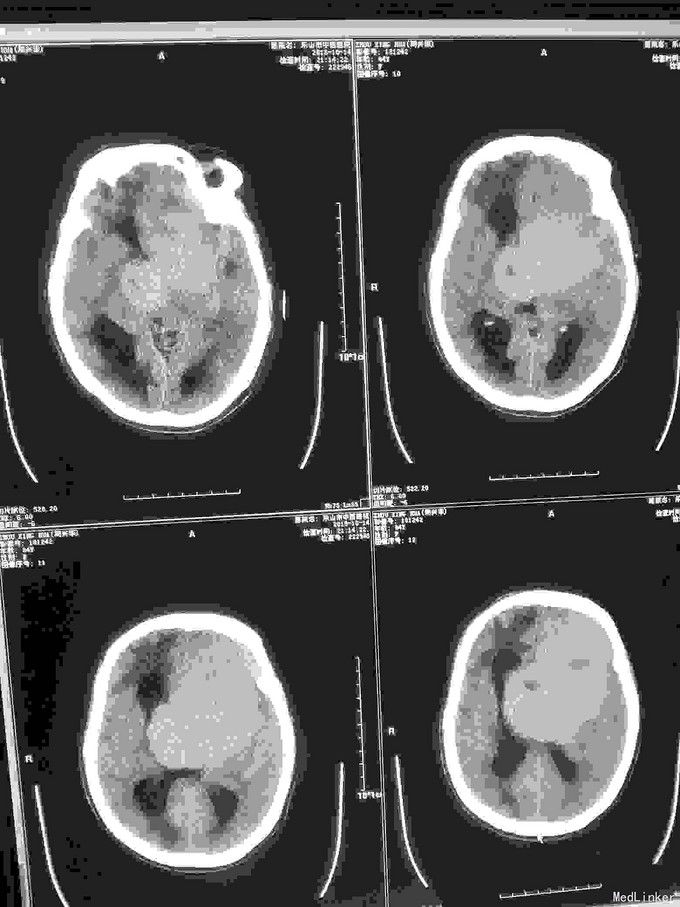

急诊CT病例

昏迷不醒就诊